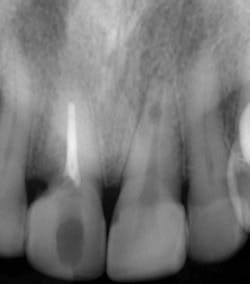

Fig. 1 — Preoperative radiograph demonstrating an internal resorptive defect in the apical third of the root in tooth No. 9. Note the cervical resorptive lesion in tooth No. 8.